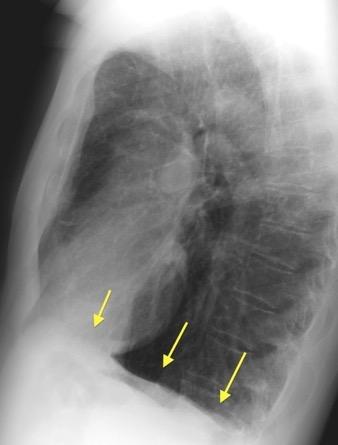

Visible en toda su longitud en ambos planos. Excepción: Parte medial en PA.

“Visible en toda su longitud en lateral”.

Consolidación por Infarto pulmonar. (TEP)